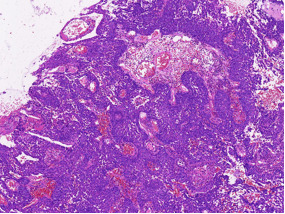

病理特征:宽薄乳头、 迷宫样内翻生长、单一肿瘤细胞形态、棘层松解、显著中性粒细胞浸润;

可见:细胞旋涡、透明细胞变、微囊形成、黏液纤毛上皮帽、部分肿瘤细胞异型性增加、坏死。

1、内翻性乳头状瘤:乳头结构简单、圆形,巢中央常形成囊腔,细胞成分复杂,包括鳞状细胞、纤毛柱状细胞和杯状细胞,可通过分子检测及AFF2 免疫组化鉴别。